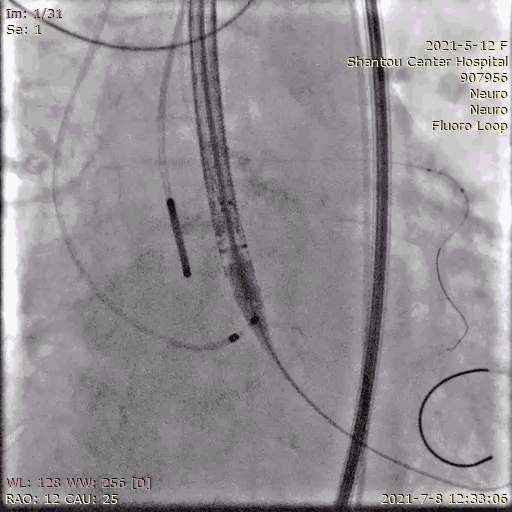

冠脉保护

指引导管将保护球囊送入左冠,防止紧急冠脉堵塞,若瓣膜释放后左冠灌注不良,则行开窗/烟囱植入冠脉支架。

送入输送系统

输送系统定位

输送系统定位,标准位置释放

120bpm起搏